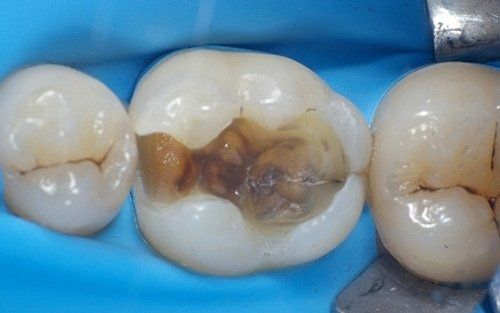

perfect disinfection and isolation of the operating field to be successfully applied. The rubber dam is a sheet of latex or silicone (some images below), invented back in 1864, available in various colours, applied to the teeth whenever treatments are carried out, whether it's a simple filling, sealant, a more complex restorative therapy (inlay and/or veneer), or endodontic therapy (root canal treatment) or adhesive cementation of a prosthetic crown. It is absolutely necessary when

old amalgam fillings need to be removed

from a tooth as it prevents the patient from ingesting the mercury contained within it. The patient, both adult and child, is